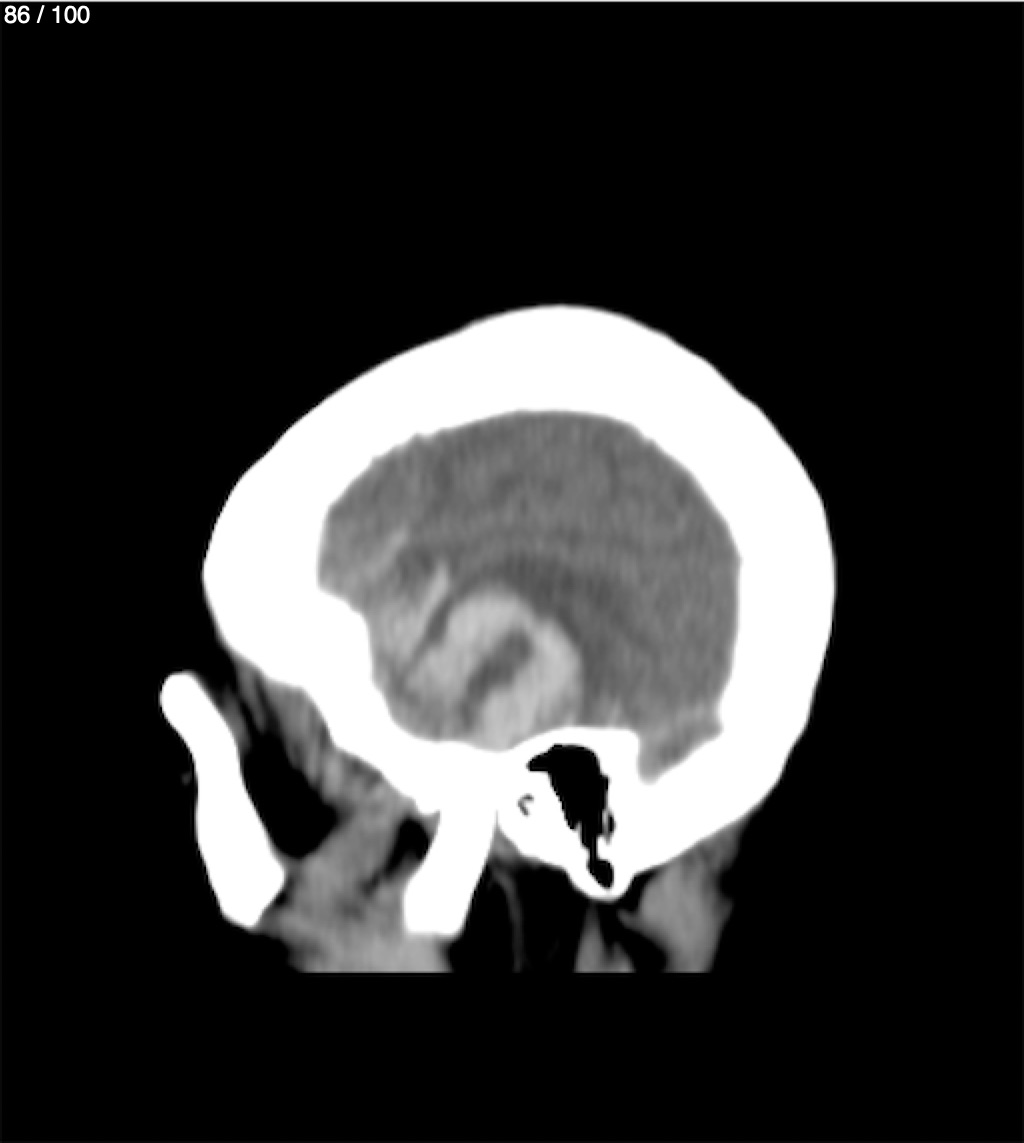

Maria Lopez Aguilar 78A - E+1 Tc Craneo